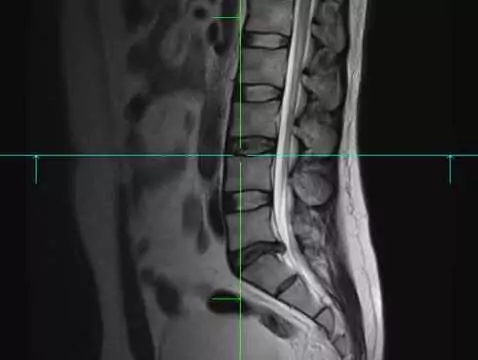

Hej. Od dłuższego czasu odczuwam ból między łopatkami i w odcinku lędźwiowym ciągnący na nogi oraz ból lewej nogi od stopy do kolana przy którym muszę w pracy zdejmować buta bo nie mogę stanąć na nogę i drętwieje mi. Odebrałam dziś wynik z RTG w opisie skolioza lewowypukła, wyraźna osteofitoza trzonów i zwężenie tarcz międzykręgowych Th12-L1-2-3. Czy to coś strasznego? Dodam że pracuje w dużym markecie spożywczo - przemyslowym